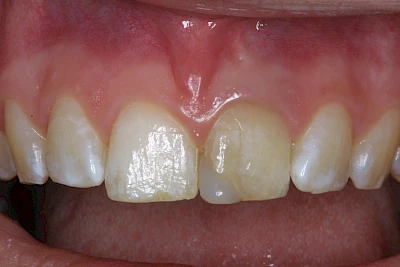

- Durch übermäßige Fluorideinlagerung in der Zahnreifung (mehrere Zähne, weißlich-fleckig)

Gerade bei Kindern und Jugendlichen werden zunehmend häufiger bräunliche Verfärbungen mitunter auch mit Formveränderungen (die Oberfläche ist rauh oder zerklüftet) der Zähne beobachtet. Meist sind Schneidezähne oder Backenzähne betroffen. Dies könnte ein Hinweis auf sogenannte Kreidezähne (MIH: Molaren-Inzisiven-Hypomineralisation) sein.